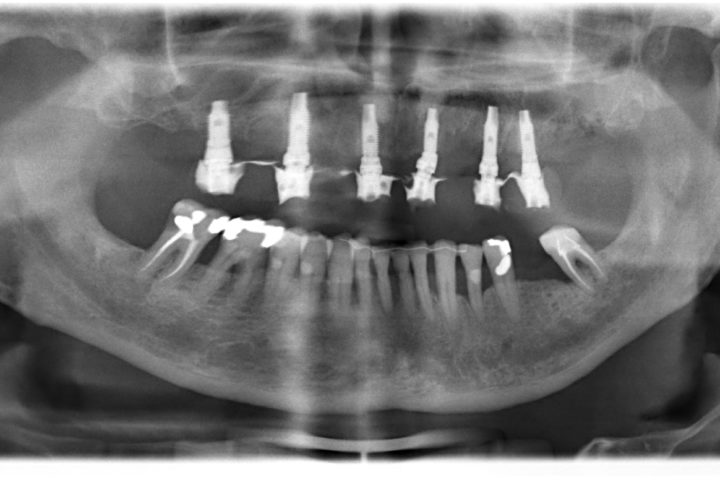

Arcata superiore - Fase iniziale, intermedia e finale